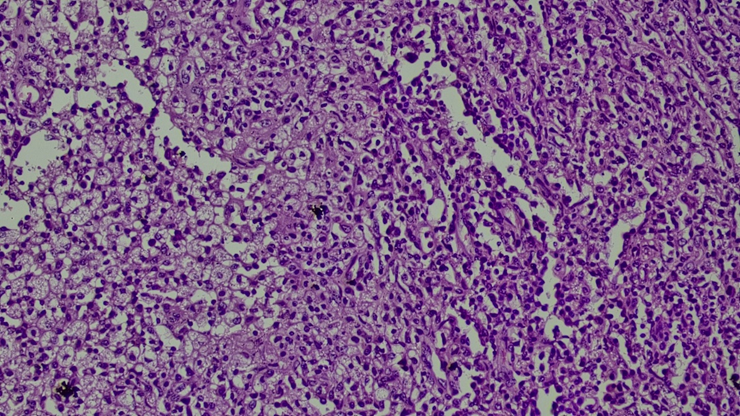

Microscopy: Sections studied from the left ovarian mass shows predominantly sheets of foamy macrophages, many histiocytes, plasma cells, binucleated plasma cells, and lymphocytes [Figure 2, Figure 3].

Areas of normal ovarian tissue were also seen. focal areas show necrosis. Occasional multinucleated giant cells seen. The left fallopian tube shows lymphoplasmacytic infiltrates along with a few macrophages.

Features are consistent with features of xanthogranulomatous oophoritis - Left ovarian mass.